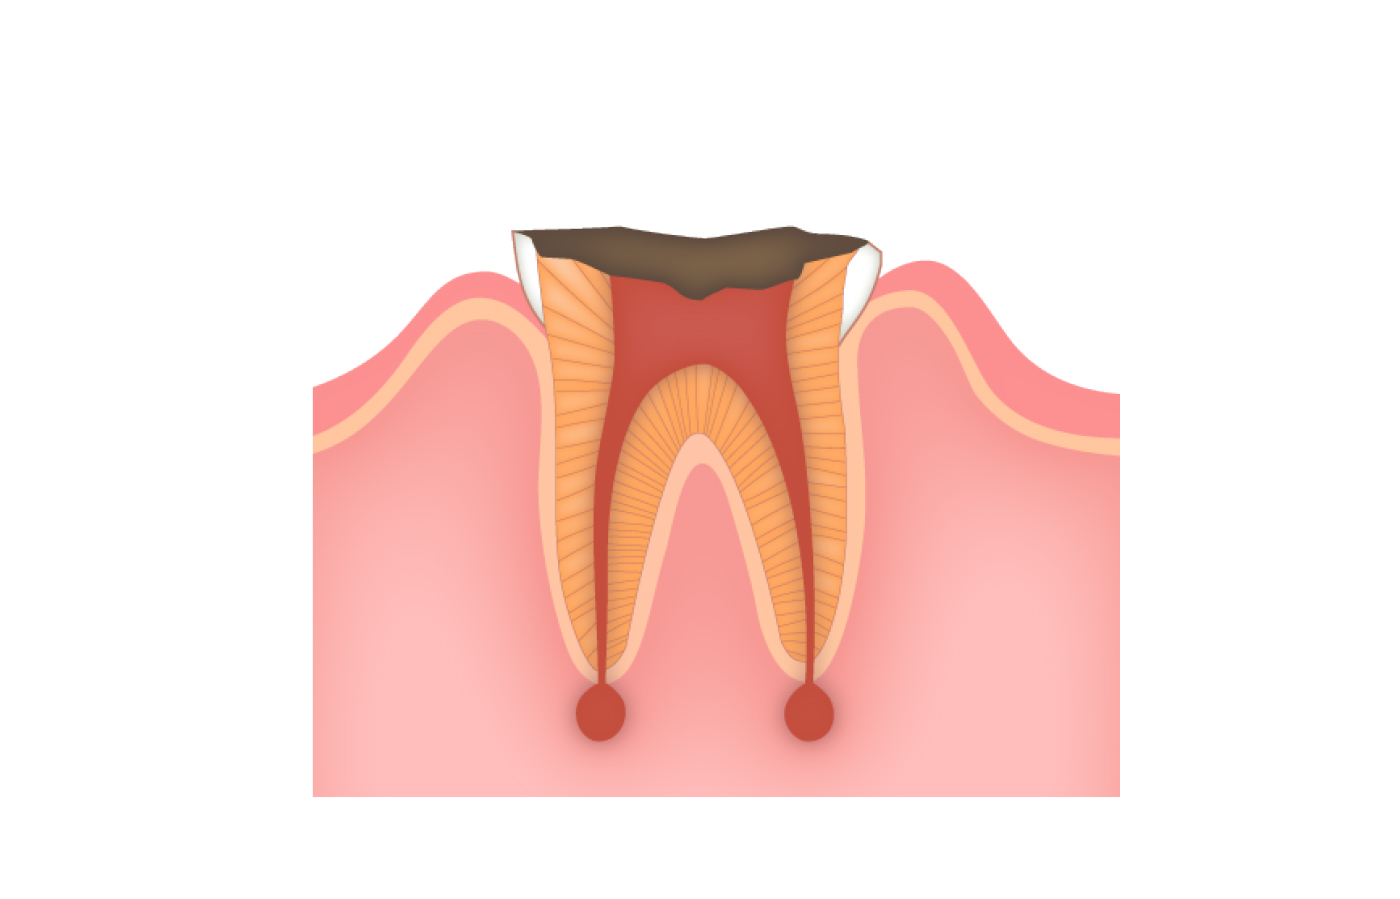

むし歯が進行して、むし歯菌による感染が神経にまで広がると、食べ物や飲み物がしみたり、ズキズキと痛んだりといった症状が現れます。そうなると、日常生活に支障が出るほど強い痛みが出たり、頬が赤く腫れることもあります。

むし歯は細菌による感染症です。放っておくと歯の表面から内部へと感染が進行します。ここでは5つの段階に分けてご説明します。

神経まで進んだむし歯(C3)

神経が感染した場合は、感染した神経と血管を取り除き、歯の内部を清掃・消毒し、無菌に近い状態にするために薬を詰めます。これが「根管治療」で、歯を抜かずに保存できる治療法です。通院回数は7〜8回で、最終的に土台を築いて被せ物をします。